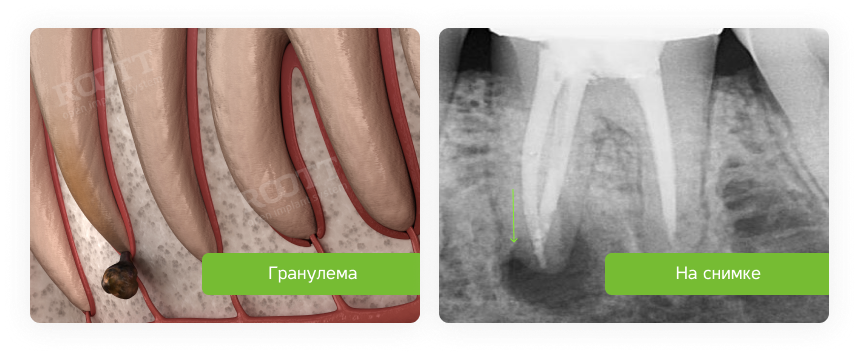

Опустились дёсны в нескольких местах, обнажились шейки зубов. Чувствительные, болят от прикосновений, могут реагировать на холодное, горячее, сладкое.

Ситуация как примерно на пик2.